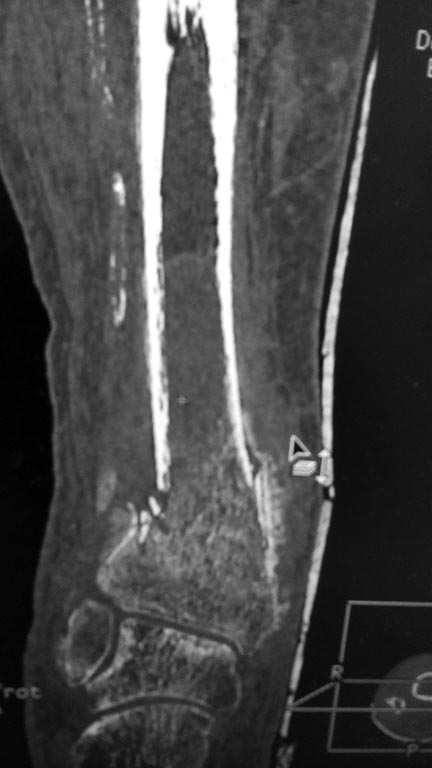

Перелом костей голени в нижней трети

Добрый день!Обратилась женщина 1958 г.р.Травма 08.09.16. Почувствовала боль в правой голени во время сна.

Лечилась амбулаторно с Ds: закрытый перелом костей правой голени в нижней трети без смещения. Повторную травму исключает. На контрольных Rg выявлено смещение отломков, признаки консолидации.

в анамнезе сахарный диабет I типа в течении 29 лет. лабильное течение. Диабетическая нефропатия. ХБП V ст. ХПН терминальная стадия. Хронический програмный гемодиализ. Ренальная остеодистрофия. Принимает лантус 6 Ед *1 раз в сутки. уровень сахара крови 12-15 ммоль\литр. Креатинин 543 мкмоль\литр, ЩФ 1270 Е\л.

А Вы то какой диагноз ставите? От чего сломалось? Ренальная остеодистрофия на фоне ХПН с гемодиализом? Диабетическая остеоартропатия? Пишете, что повторную травму исключает. Но и первичной не было. Последняя рентгенограмма (где перелом без смещения) когда была сделана? Сразу после обнаружения перелома? Там уже есть признаки консолидации. Есть ли признаки периферической нейропатии? Если не вдаваться в подробности, то можно думать об остеосинтезе двойного перелома наружной лодыжки (вероятно, уже срослась). И интрамедуллярном остеосинтезе большеберцовой кости.